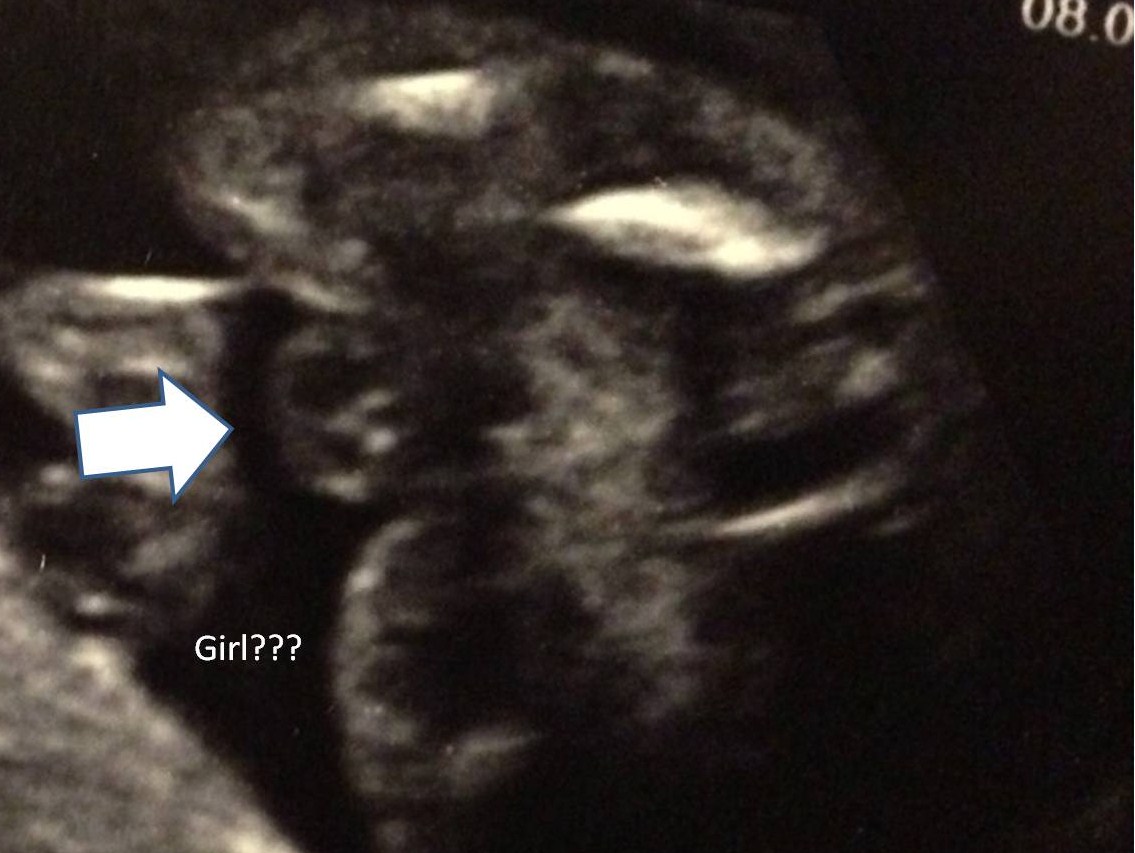

Hello :-) Is that a Boy ore a Girl? Tec said Girl I am confused -> What is the "big thing" that should be the Girl parts ??? (19 Weeks 4 Days pregnant) Thanks :-)))

Congrats that's 100% a girl, what your arrow is pointing at is her labia or lips that's a fantastic "potty shot"